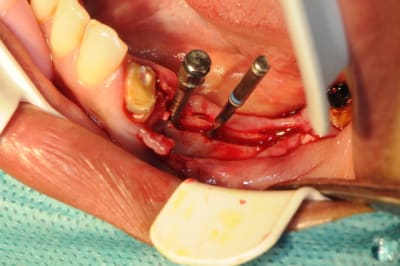

5:

évolution il faut obtenir de quoi placer un diamètre 3,4

de nouveau lame 15 pour incision de décharge verticale

6

lame 15

manuel et impacté au maillet (cool)